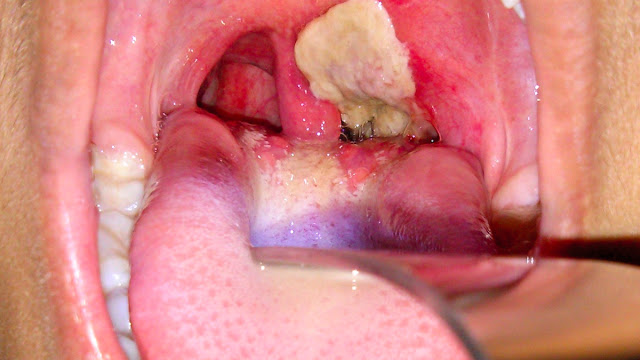

Pembebasan sitotoksin menyebabkan keradangan dan terbentuknya selaput lembut berwarna kelabu di sekitar tekak.

Sukar menelan kerana tekak berasa sakit di kawasan antara rongga mulut dan farinks dan bengkak pada kelenjar leher.

Menjangkiti tekak (tonsil, farinks, larinks, hidung) dan kadangkala selaput mukus lain, kulit , konjunktiva dan kemaluan.